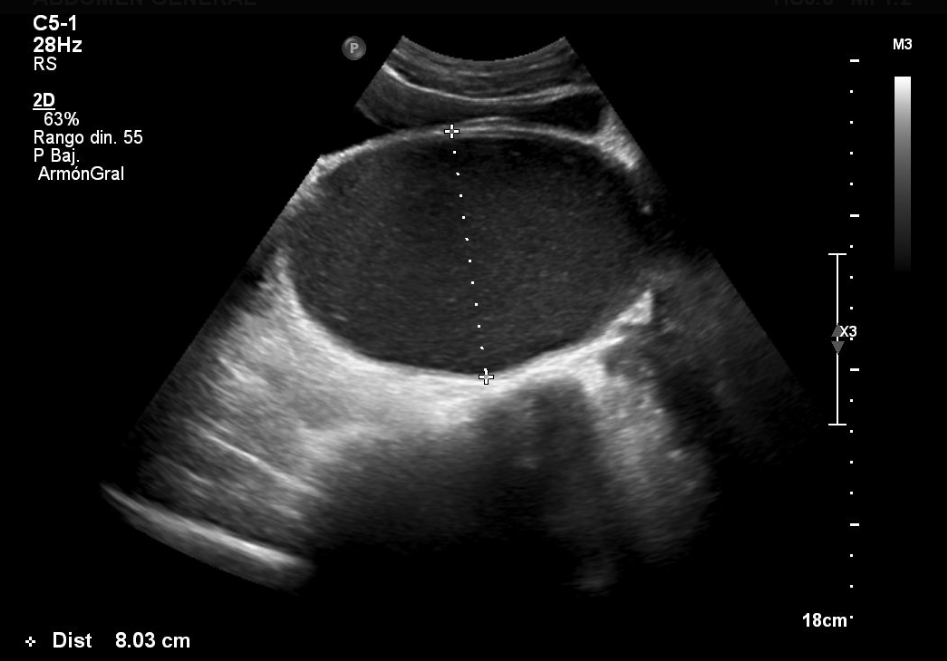

A los diez días acude de nuevo por dolor abdominal intenso que no cede con analgésicos, la despierta por la noche y tiene estreñimiento desde hace un mes. No refiere síntomas miccionales. En la exploración, el estado general es bueno, está afebril, con cardiorrespiratorio normal; se aprecia una gran tumoración abdominal móvil, fluctuante, como si tuviera contenido líquido, de forma alargada, de un tamaño aproximado de 7 × 4 cm, localizada en hipogastrio y fosa iliaca izquierda. Se solicita una ecografía abdominal urgente, en la que se observa una voluminosa lesión quística que ocupa el hipogastrio por detrás de la vejiga, con contenido ligeramente ecogénico, homogéneo, de 16,7 × 8 cm de diámetro, que sugiere como primera posibilidad de diagnóstico hematocolpos por himen imperforado (HIM) (Fig. 1).

Figura 1. Hematocolpos